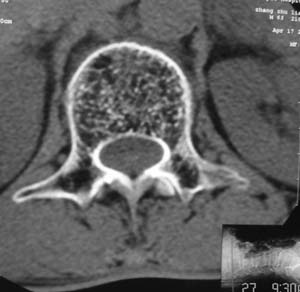

以下是引用余辉在2008-4-27 17:12:00的发言:[br]骨质疏松伴病理性压缩性骨折,椎骨骨松质密度减低,椎体骨小梁稀疏且普遍呈火柴头样改变,椎体无膨胀,无软组织肿块

以下是引用mzh123在2008-4-27 19:33:00的发言:[br]除压缩骨折表现外 还有许莫氏结节改变

以下是引用随光逐影在2008-4-27 21:29:00的发言:[br]除压缩性骨折外,还有许莫氏结节及骨质疏松表现。